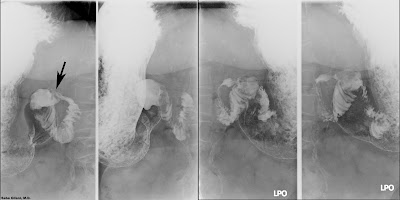

The CECT images above are from a patient who underwent sleeve gastrectomy (blue arrow) and experienced worsening abdominal pain in the weeks that followed. She was admitted with sepsis. There are necrotic areas within the spleen and multiple rim enhancing collections of air and fluid (red arrows) compatible with abscesses. Left upper quadrant fluid collections (sterile and infected) are a known complication of bariatric surgery.